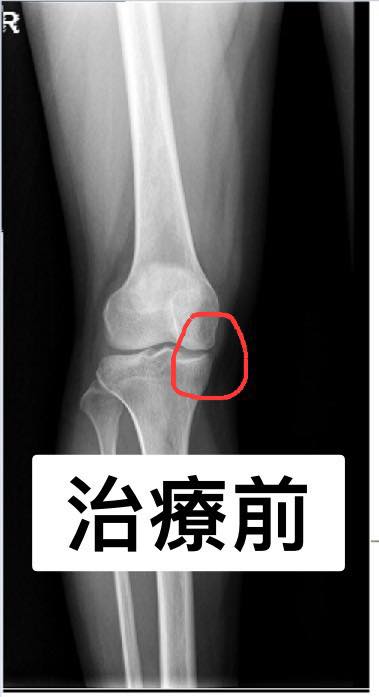

Cervical Spine Treatment Cases 膝關節案例 #退化性膝關節炎醫案 #膝關節整合針刀醫學療法 #有圖有真相前後對比照片 #內側皺襞針... 2020.10.16 #感謝中和呂小姐熱情見證 #膝關節疼痛超過十年 #看遍名醫打過五次PRP仍然沒效 #髕下脂... 2020.03.19 #退化性膝關節炎醫案 #膝關節整合針刀醫學療法 #有圖有真相前後對比照片 2019.09.07 #膝關節退化性關節炎醫案分享 #疼痛半年以上打過三次玻尿酸還痛 👉膝關節微創內側皺襞... 2019.08.15 #退化性膝關節炎醫案 #膝關節整合針刀醫學療法 #有圖有真相前後對比照片 #內側皺襞針... 2019.06.26 #膝關節疼痛兩年打了三次PRP效果不如預期怎麼辦 ▶️膝關節超微針刀整合治療如何處理 ☑️... 2019.03.17 #退化性膝關節針刀整合療法 #前後X光對比間隙打開 #針刀醫學療法讓您看到希望 2019.02.27 #退化性膝關節炎一定要開刀嗎 #除了玻尿酸或是PRP還有其他選擇嗎 #膝關節內側皺襞針刀... 2019.03.01 #退化性膝關節針刀整合療法 #前後X光對比間隙打開 #針刀醫學療法讓您看到希望 #看到患... 2019.02.16 #退化性膝關節炎第三期醫案 #治療前後影像對比 #針刀醫學療法真的做到打開膝關節間隙... 2019.02.01 #膝關節疼痛數年醫案 #謝謝八十多歲徐伯伯跟徐阿姨熱情見證針刀醫學療法 2018.12.26 1